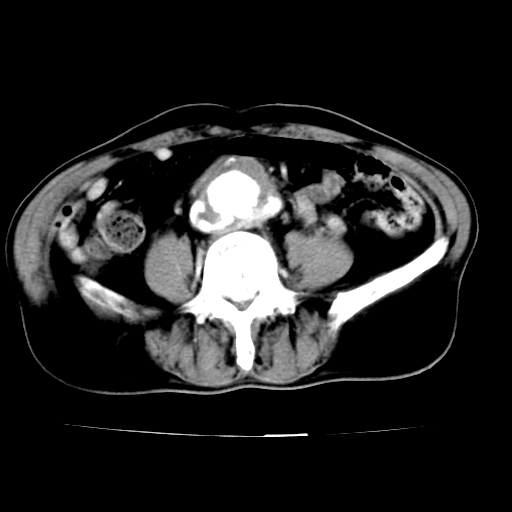

标题: V0243:右髂总动脉瘤附壁血栓形成?破裂?动静脉瘘? [打印本页]

标题: V0243:右髂总动脉瘤附壁血栓形成?破裂?动静脉瘘?

男,75岁,腹痛月余,彩超发现脐周腹主动脉异常回声。临床诊断:腹主动脉瘤。

ct诊断:右骼总动脉囊性动脉瘤并瘤内附壁血栓形成,与下腔静脉之间形成动静脉瘘。

请问各位老师:能排除动脉瘤破裂的可能吗?

各位老师注意到下腔静脉的充盈缺损了吗?注意到动静脉漏了吗?

当时是扫描的标准动脉期,可是下腔静脉与腹主动脉同步强化且幅度一致。所以我想动静脉瘘是存在的。